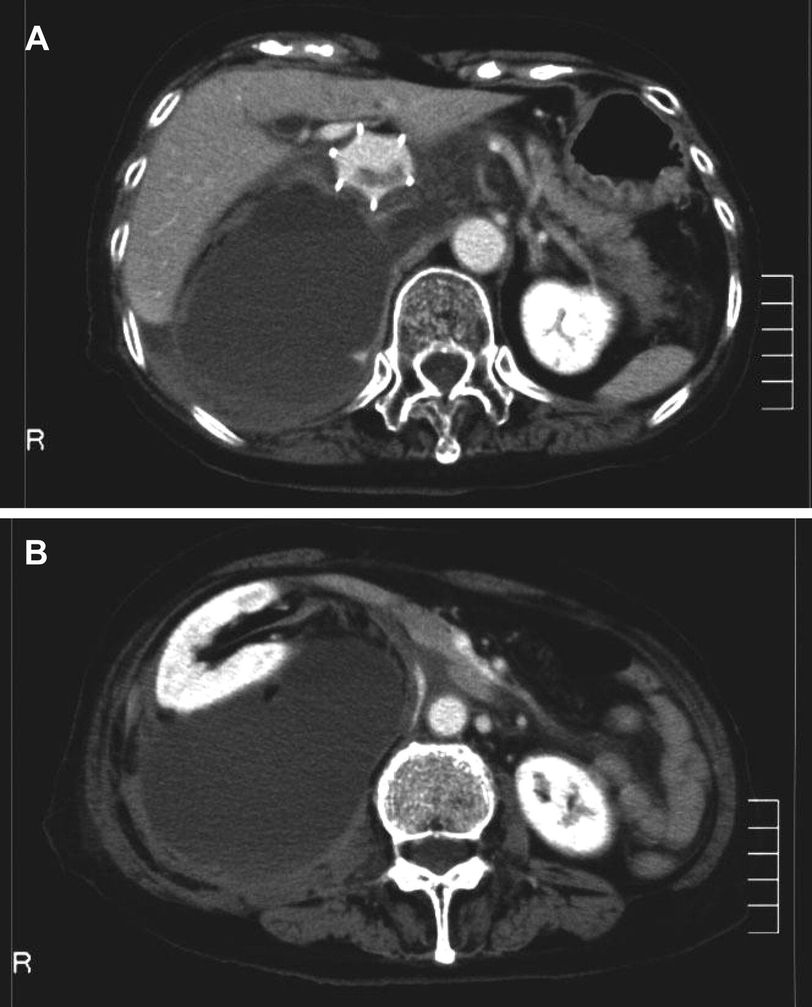

Retroperitoneal hematoma, both traumatic and nontraumatic, usually go unnoticed until the victim starts developing severe signs and symptoms of shock. Retroperitoneal hematoma can be broadly classified into three zones according to the major anatomical structures present in the region; this classification governs and modifies the management options. Zone I: Central Medial Zone It is the area between both the psoas muscles on either side. Structures such as abdominal aorta, inferior vena cava , duodenum and pancreas are present in this zone. Zone II: Perirenal Zone It is the area on either side of lateral borders of psoas muscles. Structures that are present in perirenal zone are kidneys, ureters, and portion of colon. Zone III: Pelvic Zone It is the region inferior to bifurcation of aorta. The structures in this area are external and internal iliac arteries, distal sigmoid colon, rectum, and distal portions of ureters. Preliminary procedure involves stabilization of patient according to ATLS protocol. Once the patient has stabilized, the management varies according to the zone involved. Zone I: Isolated vascular injuries are treated conservatively if no urgent laparotomy is indicated. Hemorrhage control is the key. Bowel damage can be managed by end-to-end anastomosis. Zone II: Conservative management is considered if indicated otherwise. Exploration may be required. Nephrectomy is rare. Vascular reconstruction is considered only in patients with abnormal contralateral kidney function. Zone III: Iliac vessel injuries are associated with high mortality. Intravascular techniques may be used for managing iliac vessels. Multi-disciplinary approach is required for bone fractures. Source: Approach and Management of Traumatic Retroperitoneal Injuries https://www.elsevier.es/en-revista-cirugia-espanola-english-edition--436-articulo-approach-management-traumatic-retroperitoneal-injuries-S2173507718300991 Image via https://www.ahajournals.org/doi/10.1161/CIRCULATIONAHA.107.722496